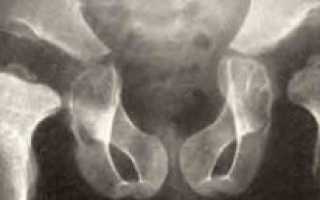

Рентгенографическое исследование тазобедренных суставов у детей, у которых заподозрена дисплазия Майера, позволило обнаружить более позднее по сравнению с нормой появление ядер оссификации. Наблюдается уменьшение в размерах либо недоразвитие хрящевой части эпифиза бедра.

Ядра окостенения появляются с запозданием, может появиться одно ядро и несколько сразу. В ряде случаев подобное приводит к ошибкам в диагностике, такое состояние расценивается, как очаги асептического некроза головки бедренной кости.

При рентгенологическом и ультразвуковом обследовании не удаётся обнаруживать экссудативных процессов в полости сустава.

В конце прогрессирования дисплазии Майера возможно обнаружить на рентгеновском снимке сформировавшийся эпифиз бедренной кости с невыраженным уменьшением его размеров. Структура костной ткани и хрящевого покрытия при этом не имеет отклонений.

Рентгенограмма и ультразвуковое обследование отображают несовпадение центральной точки головки бедренной кости с центральной точкой в вертлужной впадине.